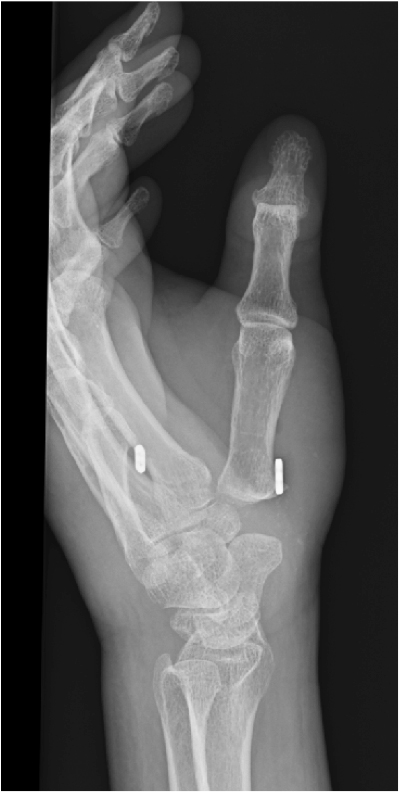

当院で行なっている手術療法には、関節固定術と関節形成術があります。関節固定術は痛みの出ているCM関節をチタン製のスクリューで固定する方法で、雪かきなどの力強い作業が多い方に適応となります。痛みはなくなりますが、関節を固定するため、親指を閉じることが難しくなります。一方、関節形成術は、痛みの原因となっている骨のうち、大菱形骨を全部もしくは部分的に摘出し、第1中手骨を人工紐で第2中手骨につり上げます(suture button suspension)。ピンチ力や握力が低下することがありますが、関節の動きを温存できるため、力強い作業よりは細かな作業をされる方に適応となります。この手術は低侵襲化が進んでおり、最近では、関節の状態により大菱形骨を摘出しない症例も出てきました。また、MP関節が過伸展した進行例では、MP関節をワイヤーで3週間まっすぐに仮固定をすることがあります。3週間の仮固定で過伸展がとれなそうな場合は、チタン製のスクリューでMP関節固定を行なうことがあります。(図2)

(図2)suture button suspension(Minitight rope Ⓡ suspension)

(図2)suture button suspension(Minitight rope ® suspension)